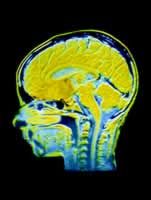

(一)非火器所致開放性腦損傷 CT檢查有助於了 解顱骨骨折、異物和碎骨片的分布.更有助於對腦損傷的了解。

(二)火器所致開放性腦損傷 除具有非火器所致開放性腦損傷的特點外,尚有彈 片或彈頭所形成的傷道特點。CT檢查對診斷和治療有很大幫助,可了解傷 道、腦挫裂傷的部位和範圍,顱骨骨折、碎骨片和異物的分布.以及有無顱內血腫和腦膿腫發生等。